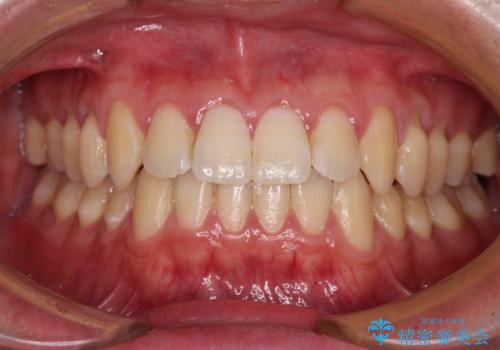

- 上下前歯のデコボコを気にして来院された患者様です。

叢生は軽微であり、費用を抑えて期間もあまりかけずに治療をしたいとのことで、インビザライン・ライトを用いて矯正治療を行うこととしました。

途中通院できなくなり、マウスピースの装着もしっかりとできなかったため、治療期間が長くかかってしまいました。